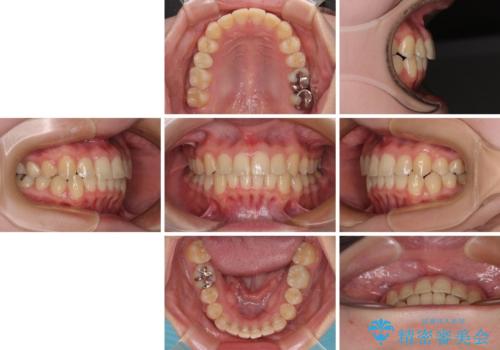

前歯のクロスバイト ギラギラのワイヤー装置で矯正治療

- 矯正装置

- メタルブラケット

- 前歯のクロスバイトを改善したいとのことで来院された患者様です。

マウスピース矯正では前歯の神経への負担が大きいことを懸念され、ワイヤー装置による矯正治療を行うこととしました。

クロスバイトが改善する際は、前歯しか接触しないため、痛みがあったり食事が取りにくかったりと、不便な時期がありますが、1年強の短期間で無事に治療を終えることができました。